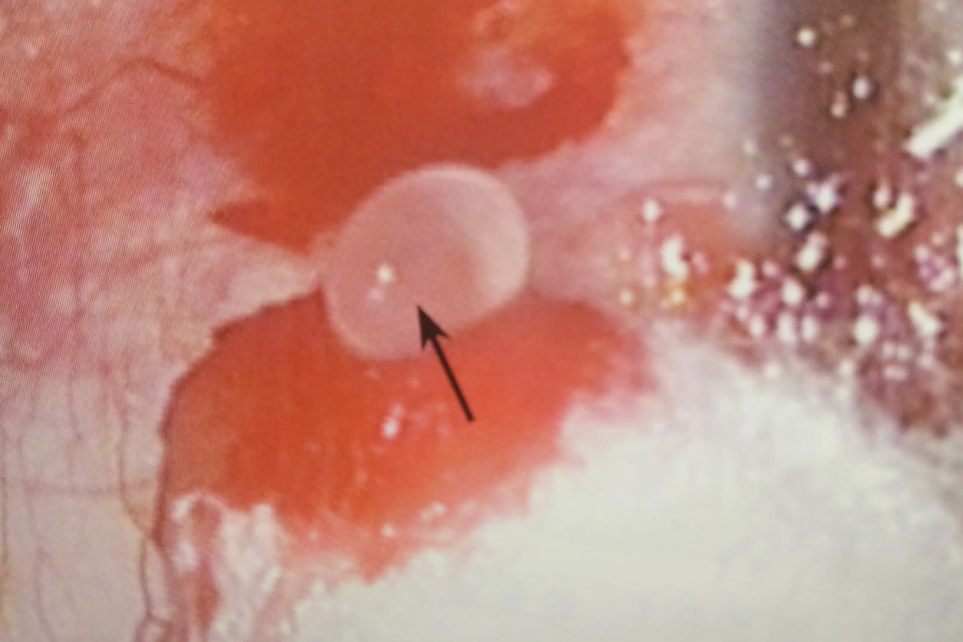

结膜淋巴管堵塞起水泡多表现为球结膜大疱或珠状局部隆起,同时还会伴随出现眼部充血、眼睛分泌物增加、咽部异物感、眼睛干涩、疼痛等症状。如果在发生结膜淋巴管堵塞后,不注意用眼卫生,还可能会引发眼部炎症,如结膜炎等。